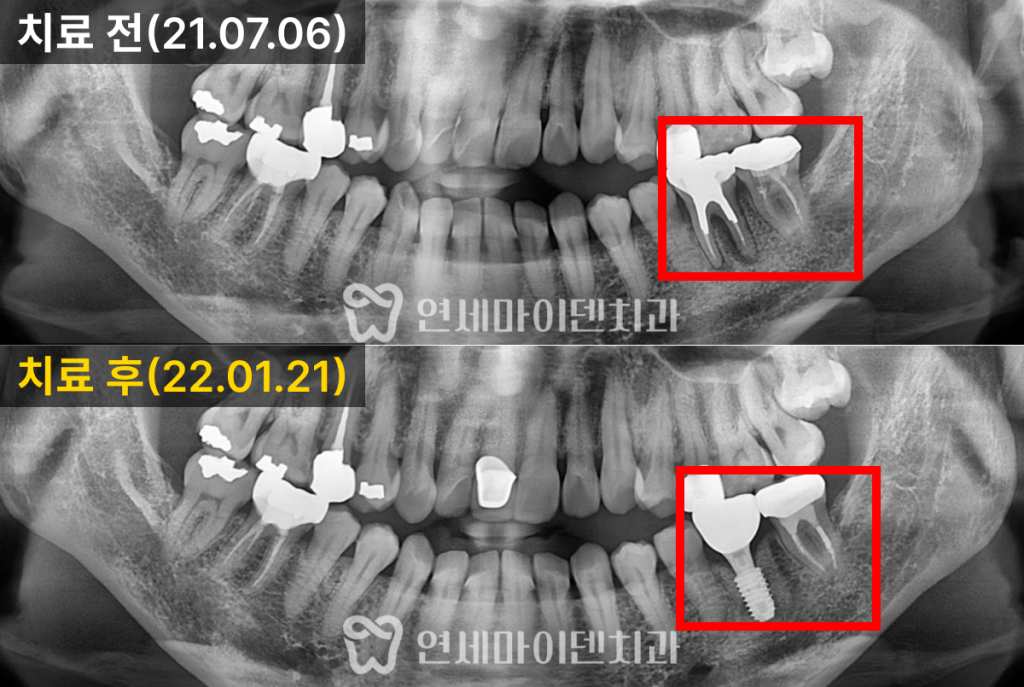

이번 케이스는

잇몸이 자주 붓고 출혈이 있으며,

고름이 반복되는 상태였습니다.

아래 어금니 한 부위

이미 크게 파절되어 있었고,

주변 잇몸에는

치석과 염증이 많이 축적되어 있었습니다.

결과적으로

염증이 심한 두 개의 치아는 발치를 결정했고,

나머지 치아는 잇몸 치료를 통해

유지하는 방향으로 계획했습니다.

임플란트 이후의 변화

3개월의 치유 기간 후

맞춤형 지대주를 이용해

최종 보철을 완성했습니다.

발치하지 않고 남겨둔 치아 주변의

잇몸뼈 레벨도

점차 안정

되는 양상을 보였습니다.

치료 후 현재까지

잇몸뼈 레벨은 안정적으로 유지되고 있습니다.